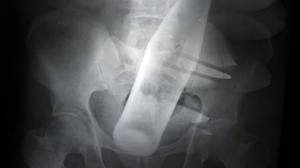

Un barbat de 46 de ani, din judetul Botosani, a ajuns la Spitalul Judetean Suceava cu o sticla cu capacitatea de 500 ml in anus. El a mers personal sa ceara sprijinul medicilor din Suceava. Botosaneanul i-a povestit unui paznic al spitalului ca si-a introdus sticla în timp ce urmărea filme pentru adulți. Bărbatul a […]